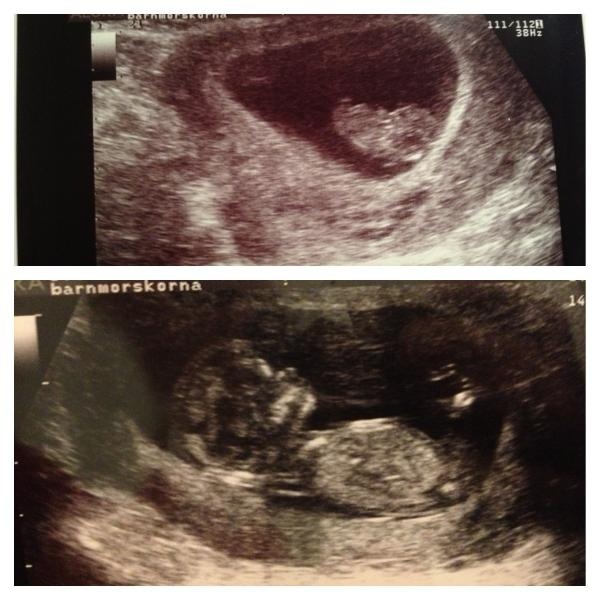

Jag tänkte att vi kunde ha ett bild forum där vi kan lägga ut bilder på våra magar hur dom växer och blir fina.